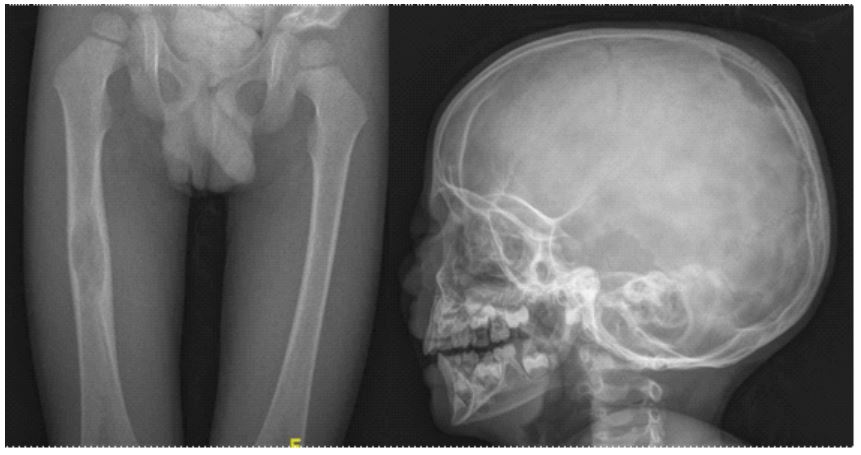

Skeletal survey was performed, finding radiolucent images corresponding to osteolytic lesions in the skull, pelvis and right femur (Figure 2). Brain MRI showed thickening of the pituitary stalk with total absence of neurohypophysis.

Figure 2: Bone radiographs showing radiolucent lesions in the right femoral diaphysis and skull.